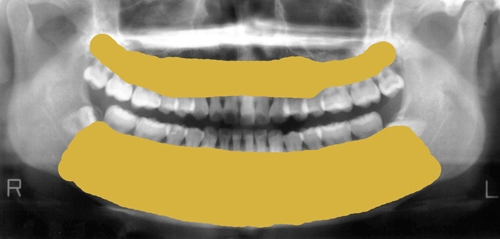

骨の病気ですので、診断にはまずはレントゲンの撮影が必要です。

もっと詳しく診断するにはCT装置による撮影を行い、

歯を支えている骨(歯槽骨)や顎の骨、

顎関節の状態まで確認することが必要になります。

骨の病気ですので、診断にはまずはレントゲンの撮影が必要です。

もっと詳しく診断するにはCT装置による撮影を行い、

歯を支えている骨(歯槽骨)や顎の骨、

顎関節の状態まで確認することが必要になります。